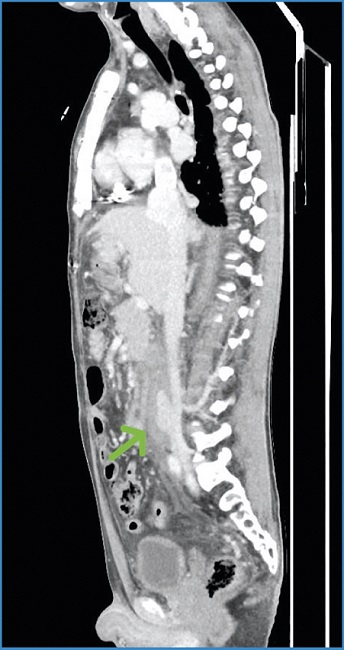

A los dos meses el paciente acudió a consultas de Cirugía Vascular. Presentaba buen estado general. El angio-TAC reveló la completa resolución del pseudoaneurisma de la VCI y del hematoma retroperitoneal (Fig. 2).

Figura 2. Angio-TAC a los dos meses. Completa resolución del pseudoaneurisma y del hematoma retroperitoneal.